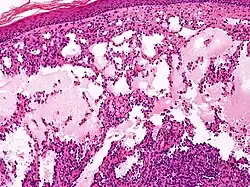

Microscopically, the vesicles in lymphangioma circumscriptum are greatly dilated lymph channels that cause the papillary dermis to expand. They may be associated with acanthosis and hyperkeratosis. There are many channels in the upper dermis which often extend to the subcutis (the deeper layer of the dermis, containing mostly fat and connective tissue). The deeper vessels have large calibers with thick walls which contain smooth muscle. The lumen is filled with lymphatic fluid, but often contains red blood cells, lymphocytes, macrophages, and neutrophils. The channels are lined with flat endothelial cells. The interstitium has many lymphoid cells and shows evidence of fibroplasia (the formation of fibrous tissue). Nodules (A small mass of tissue or aggregation of cells) in cavernous lymphangioma are large, irregular channels in the reticular dermis and subcutaneous tissue that are lined by a single layer of endothelial cells. Also an incomplete layer of smooth muscle also lines the walls of these channels. The stroma consists of loose connective tissue with a lot of inflammatory cells. These tumors usually penetrate muscle. Cystic hygroma is indistinguishable from cavernous lymphangiomas on histology.[7]